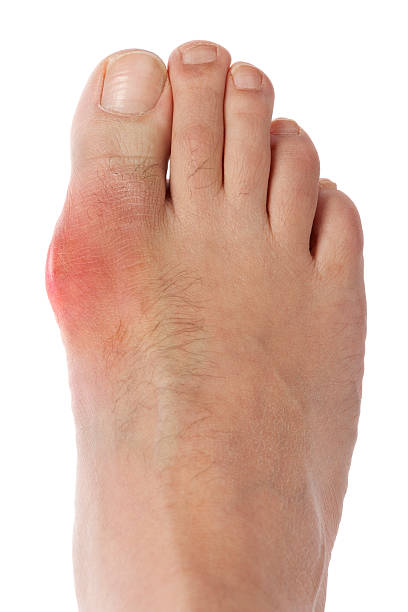

급성 통풍 발작은 갑작스럽게 발생하며, 대개 하루 이내에 최대 발생점에 도달합니다. 발작이 발생하면 통증이 극심하게 시작되고, 발적 부위는 붉고 따끔거리며 따끔거리고, 적출물로 인해 부어오릴 수 있습니다.

급성 통풍 발작은 관절 내부에서 염증이 발생합니다. 이는 염증을 일으키는 화학 물질이 적출물로 발적 주위에 축적되기 때문입니다. 염증은 일반적으로 통증, 붓기, 붉어짐 등을 초래할 수 있습니다.

발적

발적 부위는 붉고 따끔거리며, 적출물로 인해 부어오를 수 있습니다. 이러한 발적은 대개 발작이 발생하는 부위에 나타나며, 발적이 심한 경우 걷는 것이 어려울 수 있습니다.